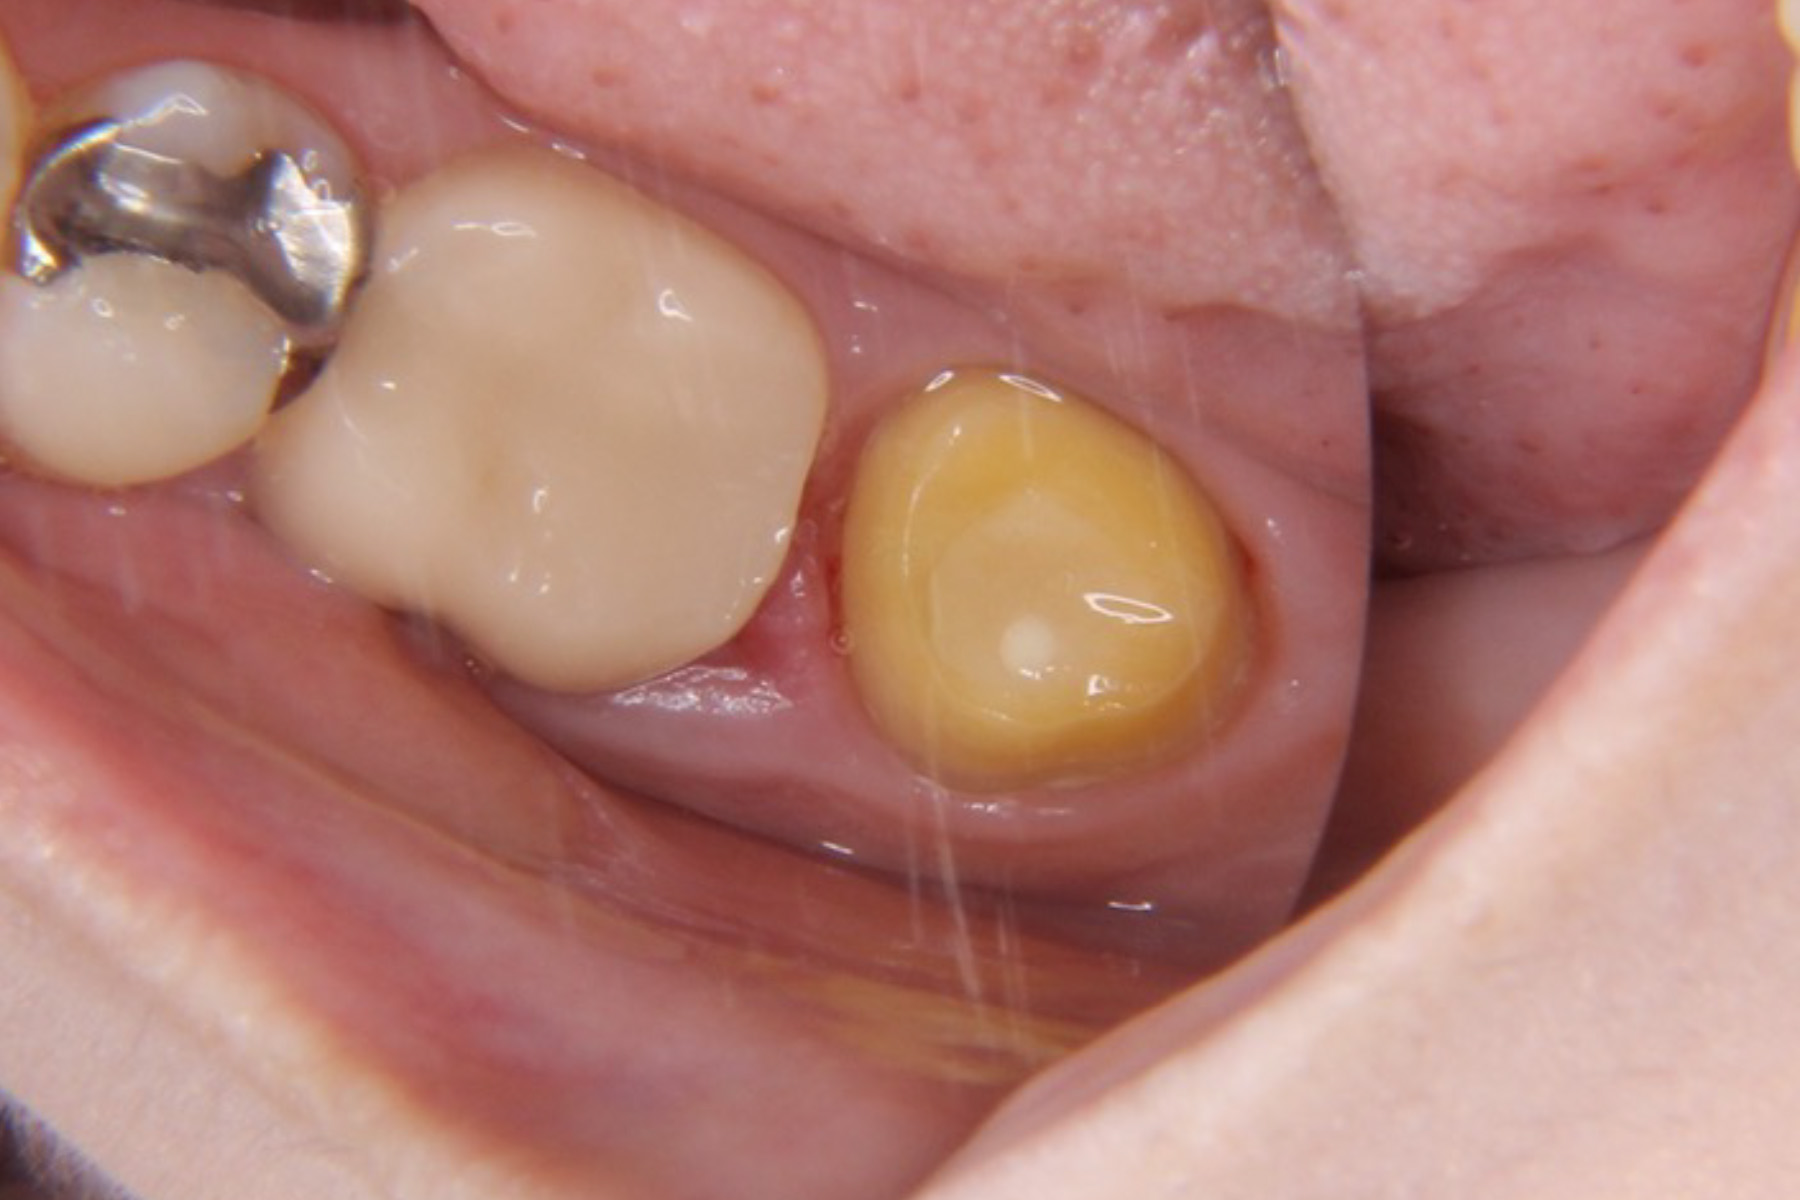

| 主訴 | 右下奥歯が膿んでいる。 |

|---|---|

| 治療内容 | 右下7番は歯根破折により抜歯が推奨された。親知らずの状態も良かった為抜歯と同時に歯牙移植手術を実施し、実質的に機能歯の喪失を防いだ。 |

| 治療期間 | 4〜6ヶ月 |

| 治療費 | 約¥50,000〜 |

| 治療リスク | 生着せず抜け落ちてしまうこともある。 |